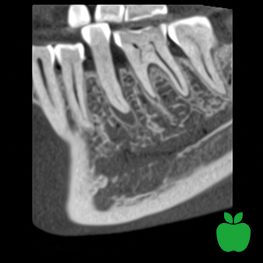

Ideal balans mellan kvalitet och stråldos

Det banbrytande lågdos-protokollet är baserat på intelligenta algoritmer som minskar den effektiva patientdosen betydligt utan någon minskning av bildkvaliteten. Det hjälper alla slags kliniker att följa ALARA-principen (As Low As Reasonably Achievable).